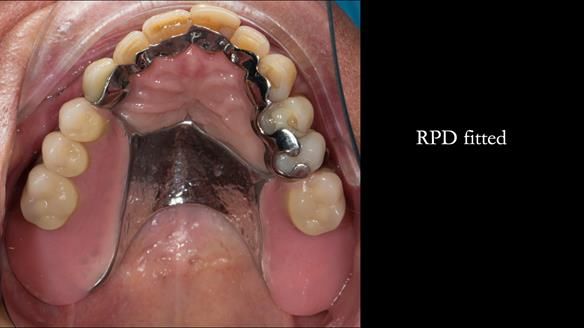

A metal-based upper RPD was made,

with metal backings incorporated to future-proof the design

should further teeth fail.

The way Rowan lengthened the teeth — particularly in the upper RPD — to match the existing gingival recession on the remaining teeth was superb. The dentures sit naturally within the context of the rest of the mouth.

Most importantly, Ken could eat comfortably, speak normally, and get on with his life without thinking about his teeth. There were no ongoing problems. No drama. No repeated interventions.